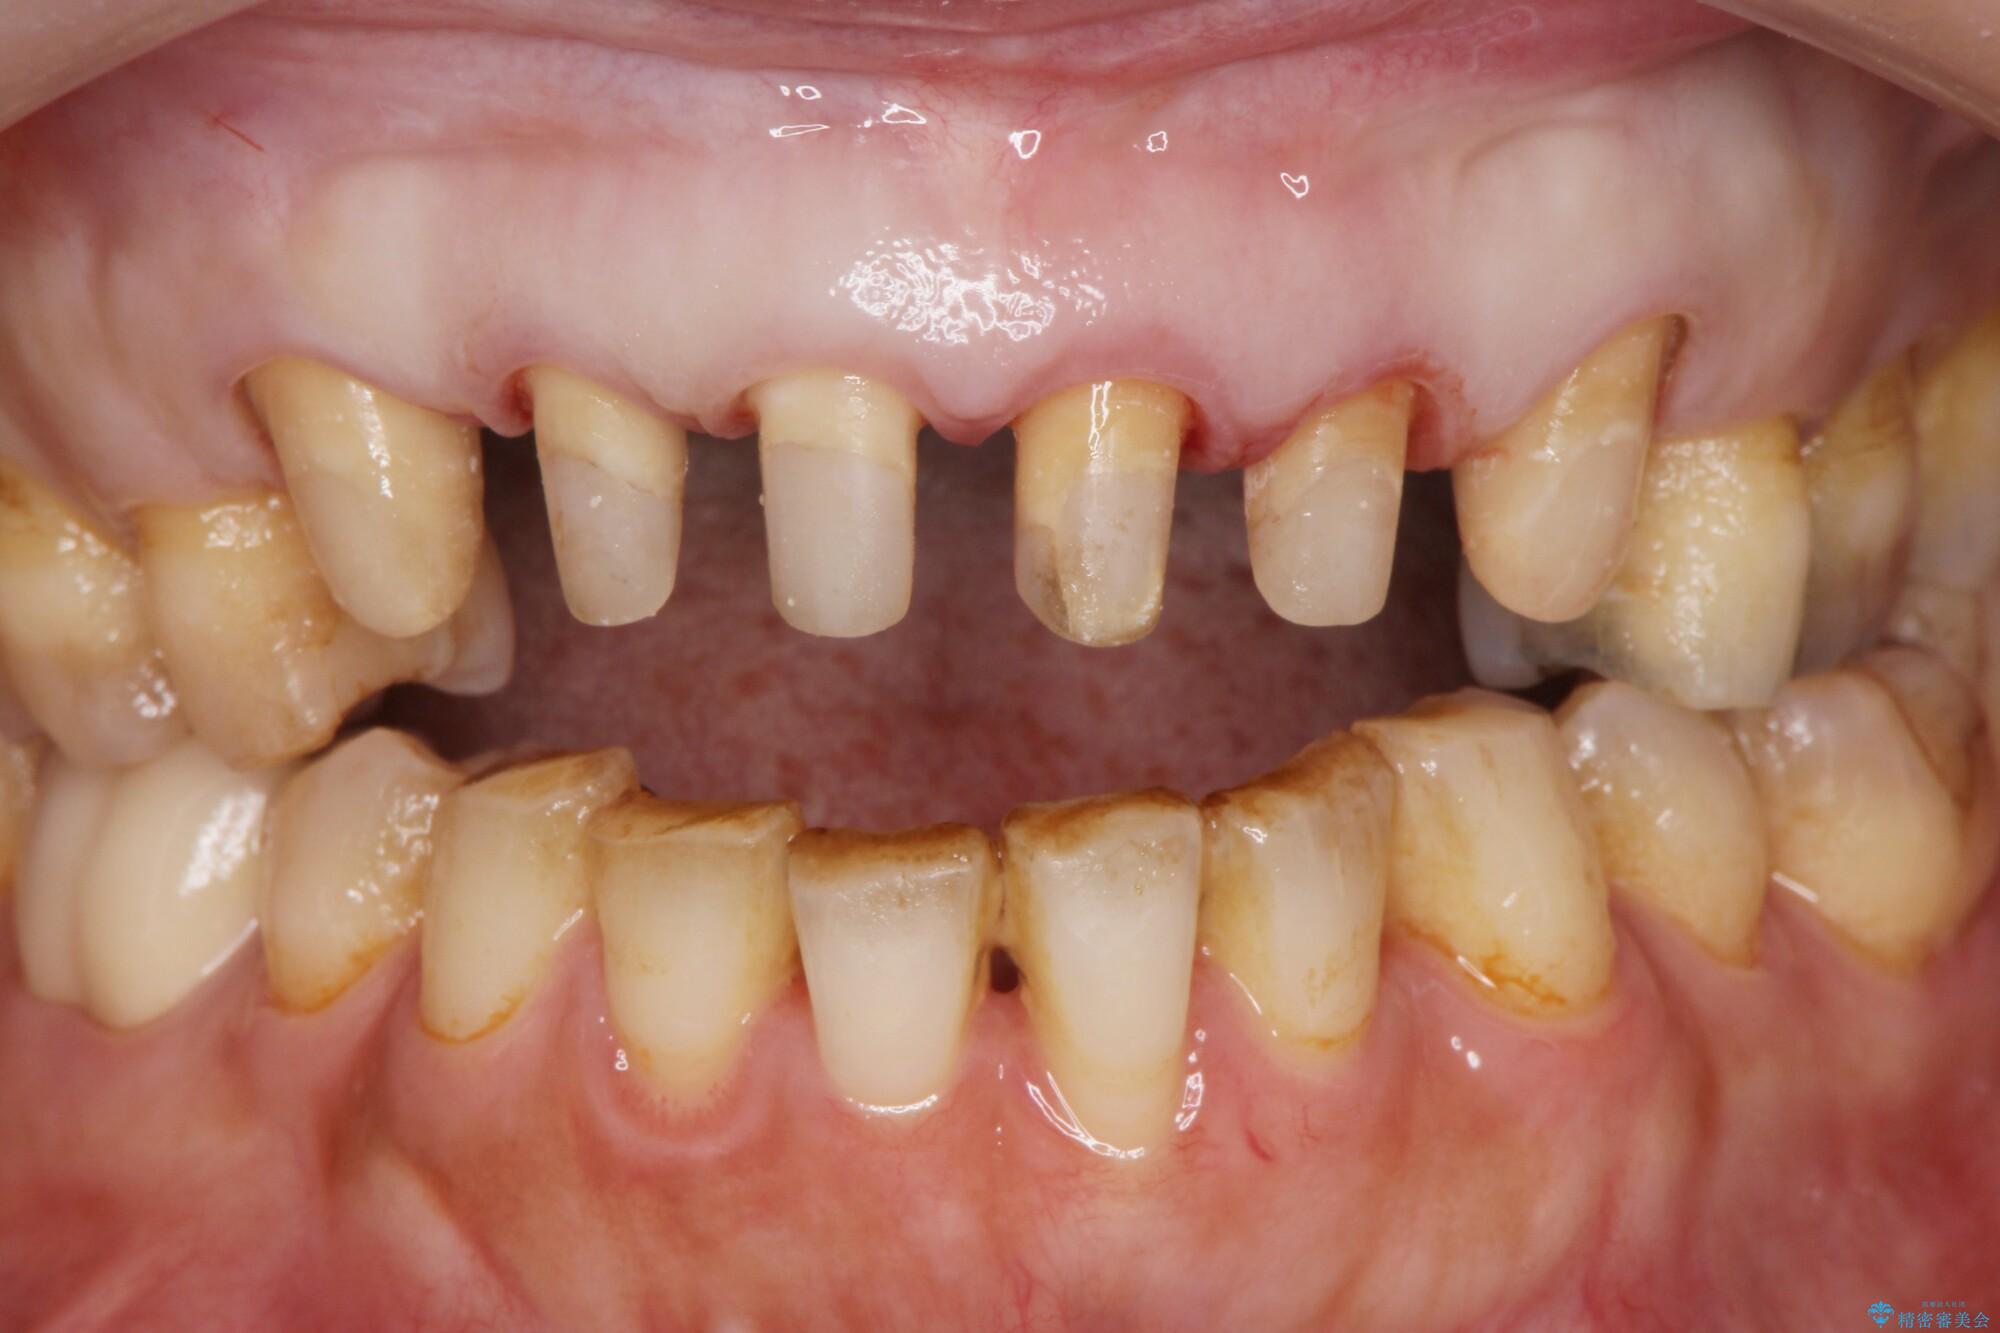

装着されていたセラミックを除去したところ、歯ぐきの奥深くまで歯牙は削られ、歯ぐきの炎症・出血が著しくみられる状態でした。

この状態で再度セラミッククラウンの作製・装着を行ってもまた同じ状態となってしまうため、歯周外科を行い歯ぐきの状態を整備したのちセラミッククラウン治療をおこなっていきます。